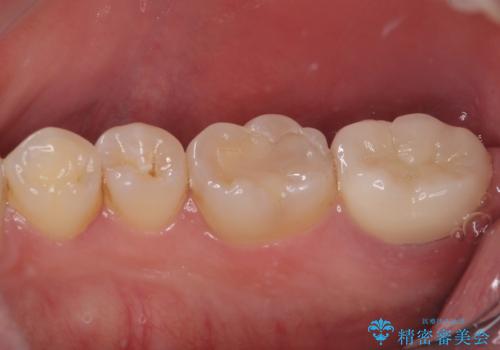

その後は速やかに根管治療を行い、初回の処置以降は痛みや違和感が一気に引いたため、根管治療後にオールセラミッククラウンにて補綴治療を行うこととしました。

治療後は一切痛みや違和感を感じることなく、快適に過ごすことができています。

診断には苦労しましたが、誤った処置を行うことなく、無事に治療を終えることができました。